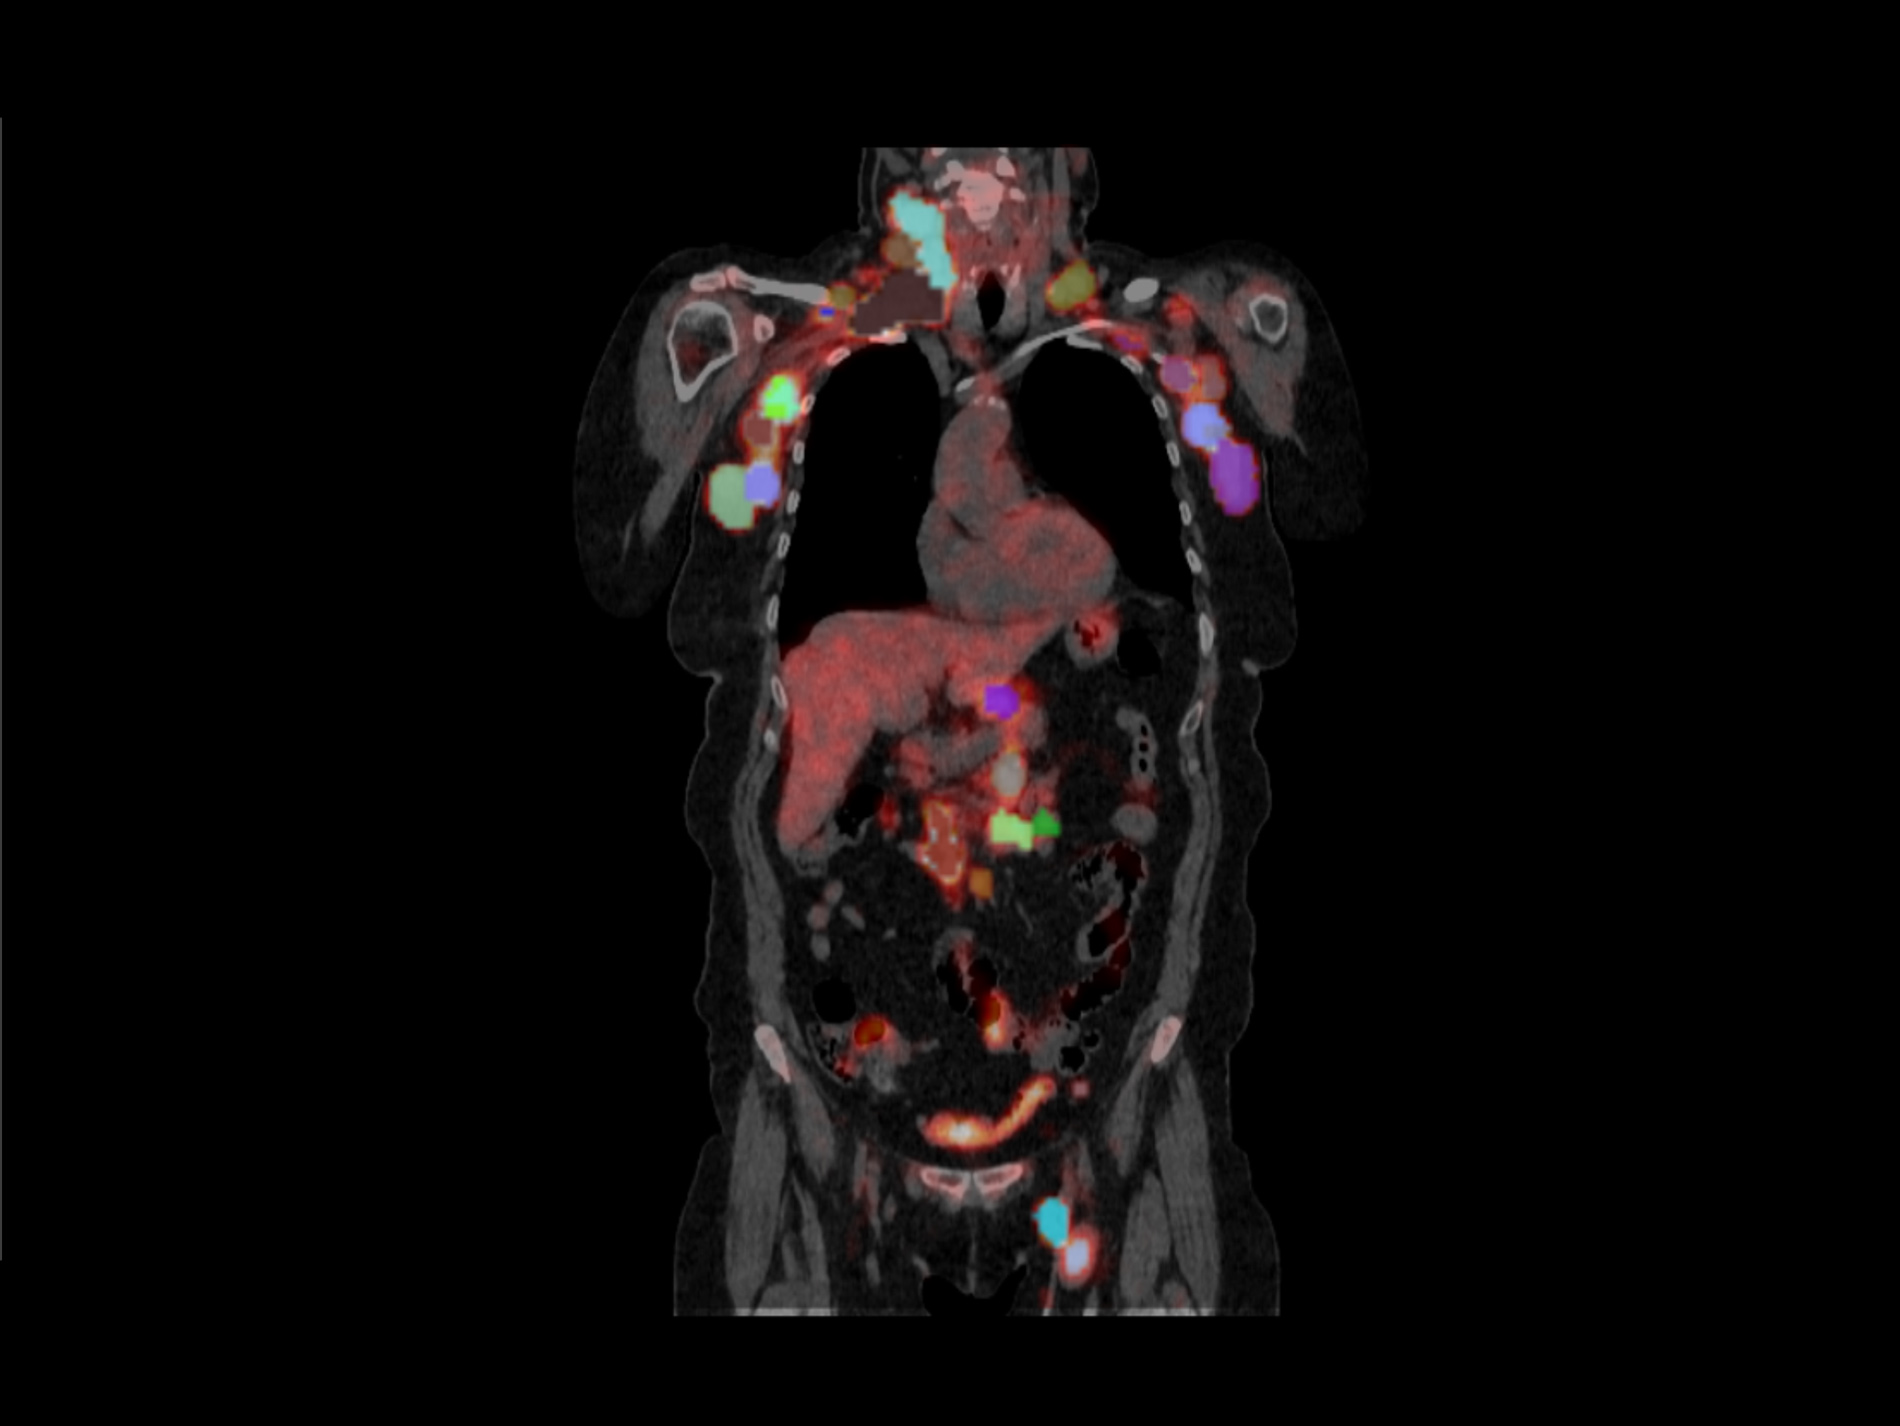

In this multicentric retrospective study, Quibim developed advanced imaging-based prognostic and predictive models using logistic regression and Cox proportional-hazards models to predict CAR-T therapy response at 3 and 6 months, overall survival (OS), progression-free survival (PFS), and the occurrence of ICANS.

Sixty-five relapsed/refractory (R/R) B-cell lymphoma patients treated with CAR-T cells were included. All visible lesions from pre-treatment 18F-FDG PET/CT scans were segmented, and quantitative imaging features were extracted using the QP-Insights® platform. Quantitative imaging features were combined with relevant clinical variables to develop prognostic and predictive models.